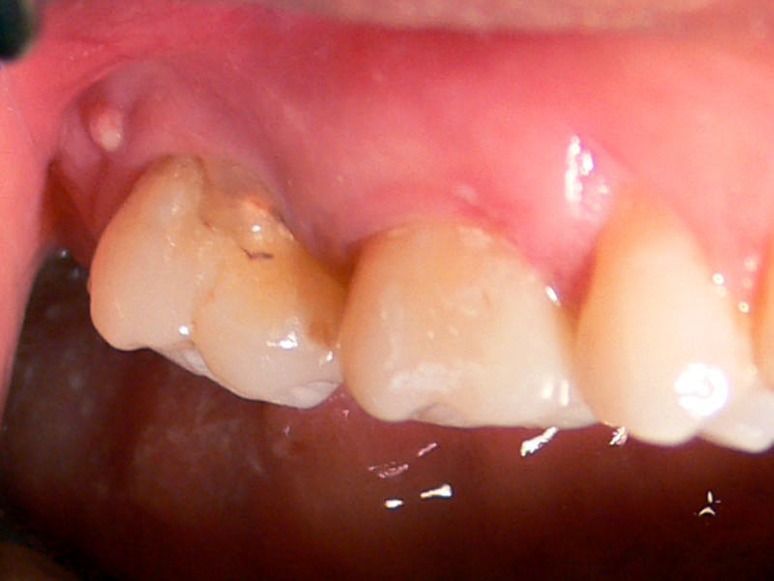

16. A 58-year-old woman was referred with a painful tooth .

A draining sinus tract was noted leading from the gingiva of the involved tooth.

What is the most appropriate description of this lesion ?